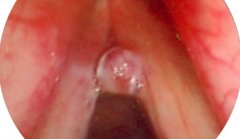

声带息肉

声带息肉是指发生于一侧声带的前中部边缘的灰白色,表面光滑的息肉样组织,多为一侧单发或多发,有蒂或广基,常呈灰白色半透明样,或为红色小突起,有 ...[详情]

声带息肉是指发生在声带边缘的增厚组织,可局限也可以弥漫,其中弥漫性者又称做息肉样变,主要病理改变在粘膜固有层,多为单侧。可能与炎症,变态反应 ...[详情]